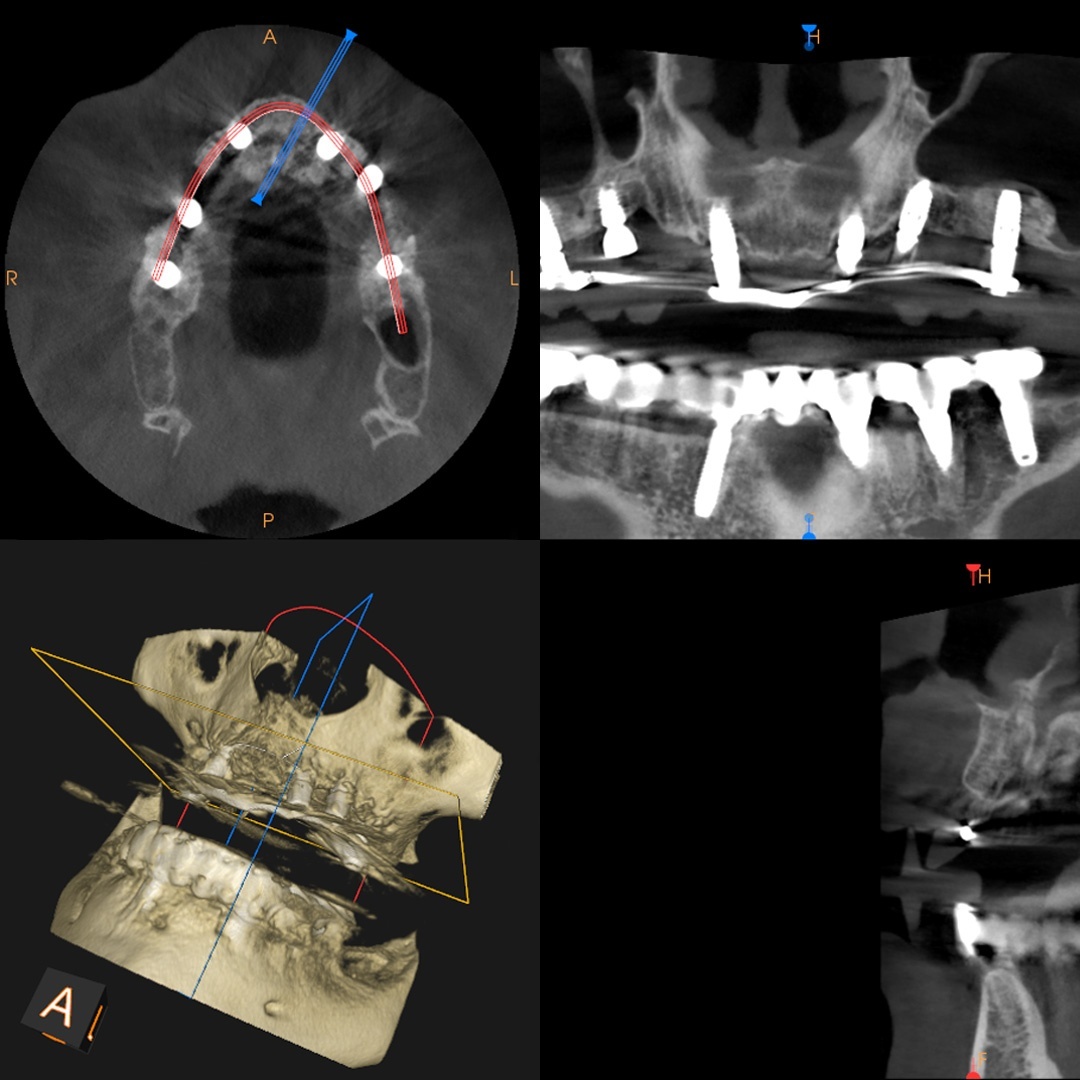

Et tannimplantat er en liten skrue av titan som kirurgisk festes direkte inn i kjevebenet. Et implantat erstatter en manglende tann eller rot og kan utstyres med en krone eller andre proteseløsninger som tannbroer eller proteser.

Etter implantatet er satt inn, så er tilhelingsperioden 3 til 6 måneder. Under tilhelingsprosessen, som kalles osseointegrasjon, vokser implantatet fast i tannbeinet.

Etter tilhelingsperioden så kan arbeidet med kronen, tannbroen eller protesen begynne. Resultatet er svært funksjonelt, langvarig og veldig estetisk.